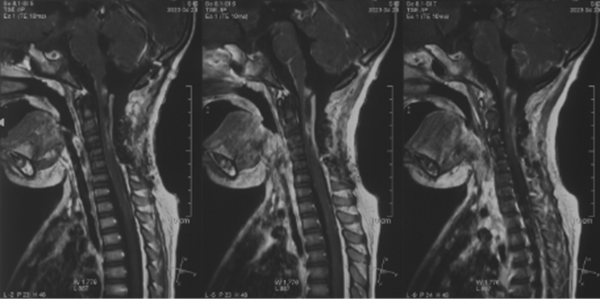

术前影像学检查

平扫MRI

显示延髓颈髓占位

增强MRI

CT